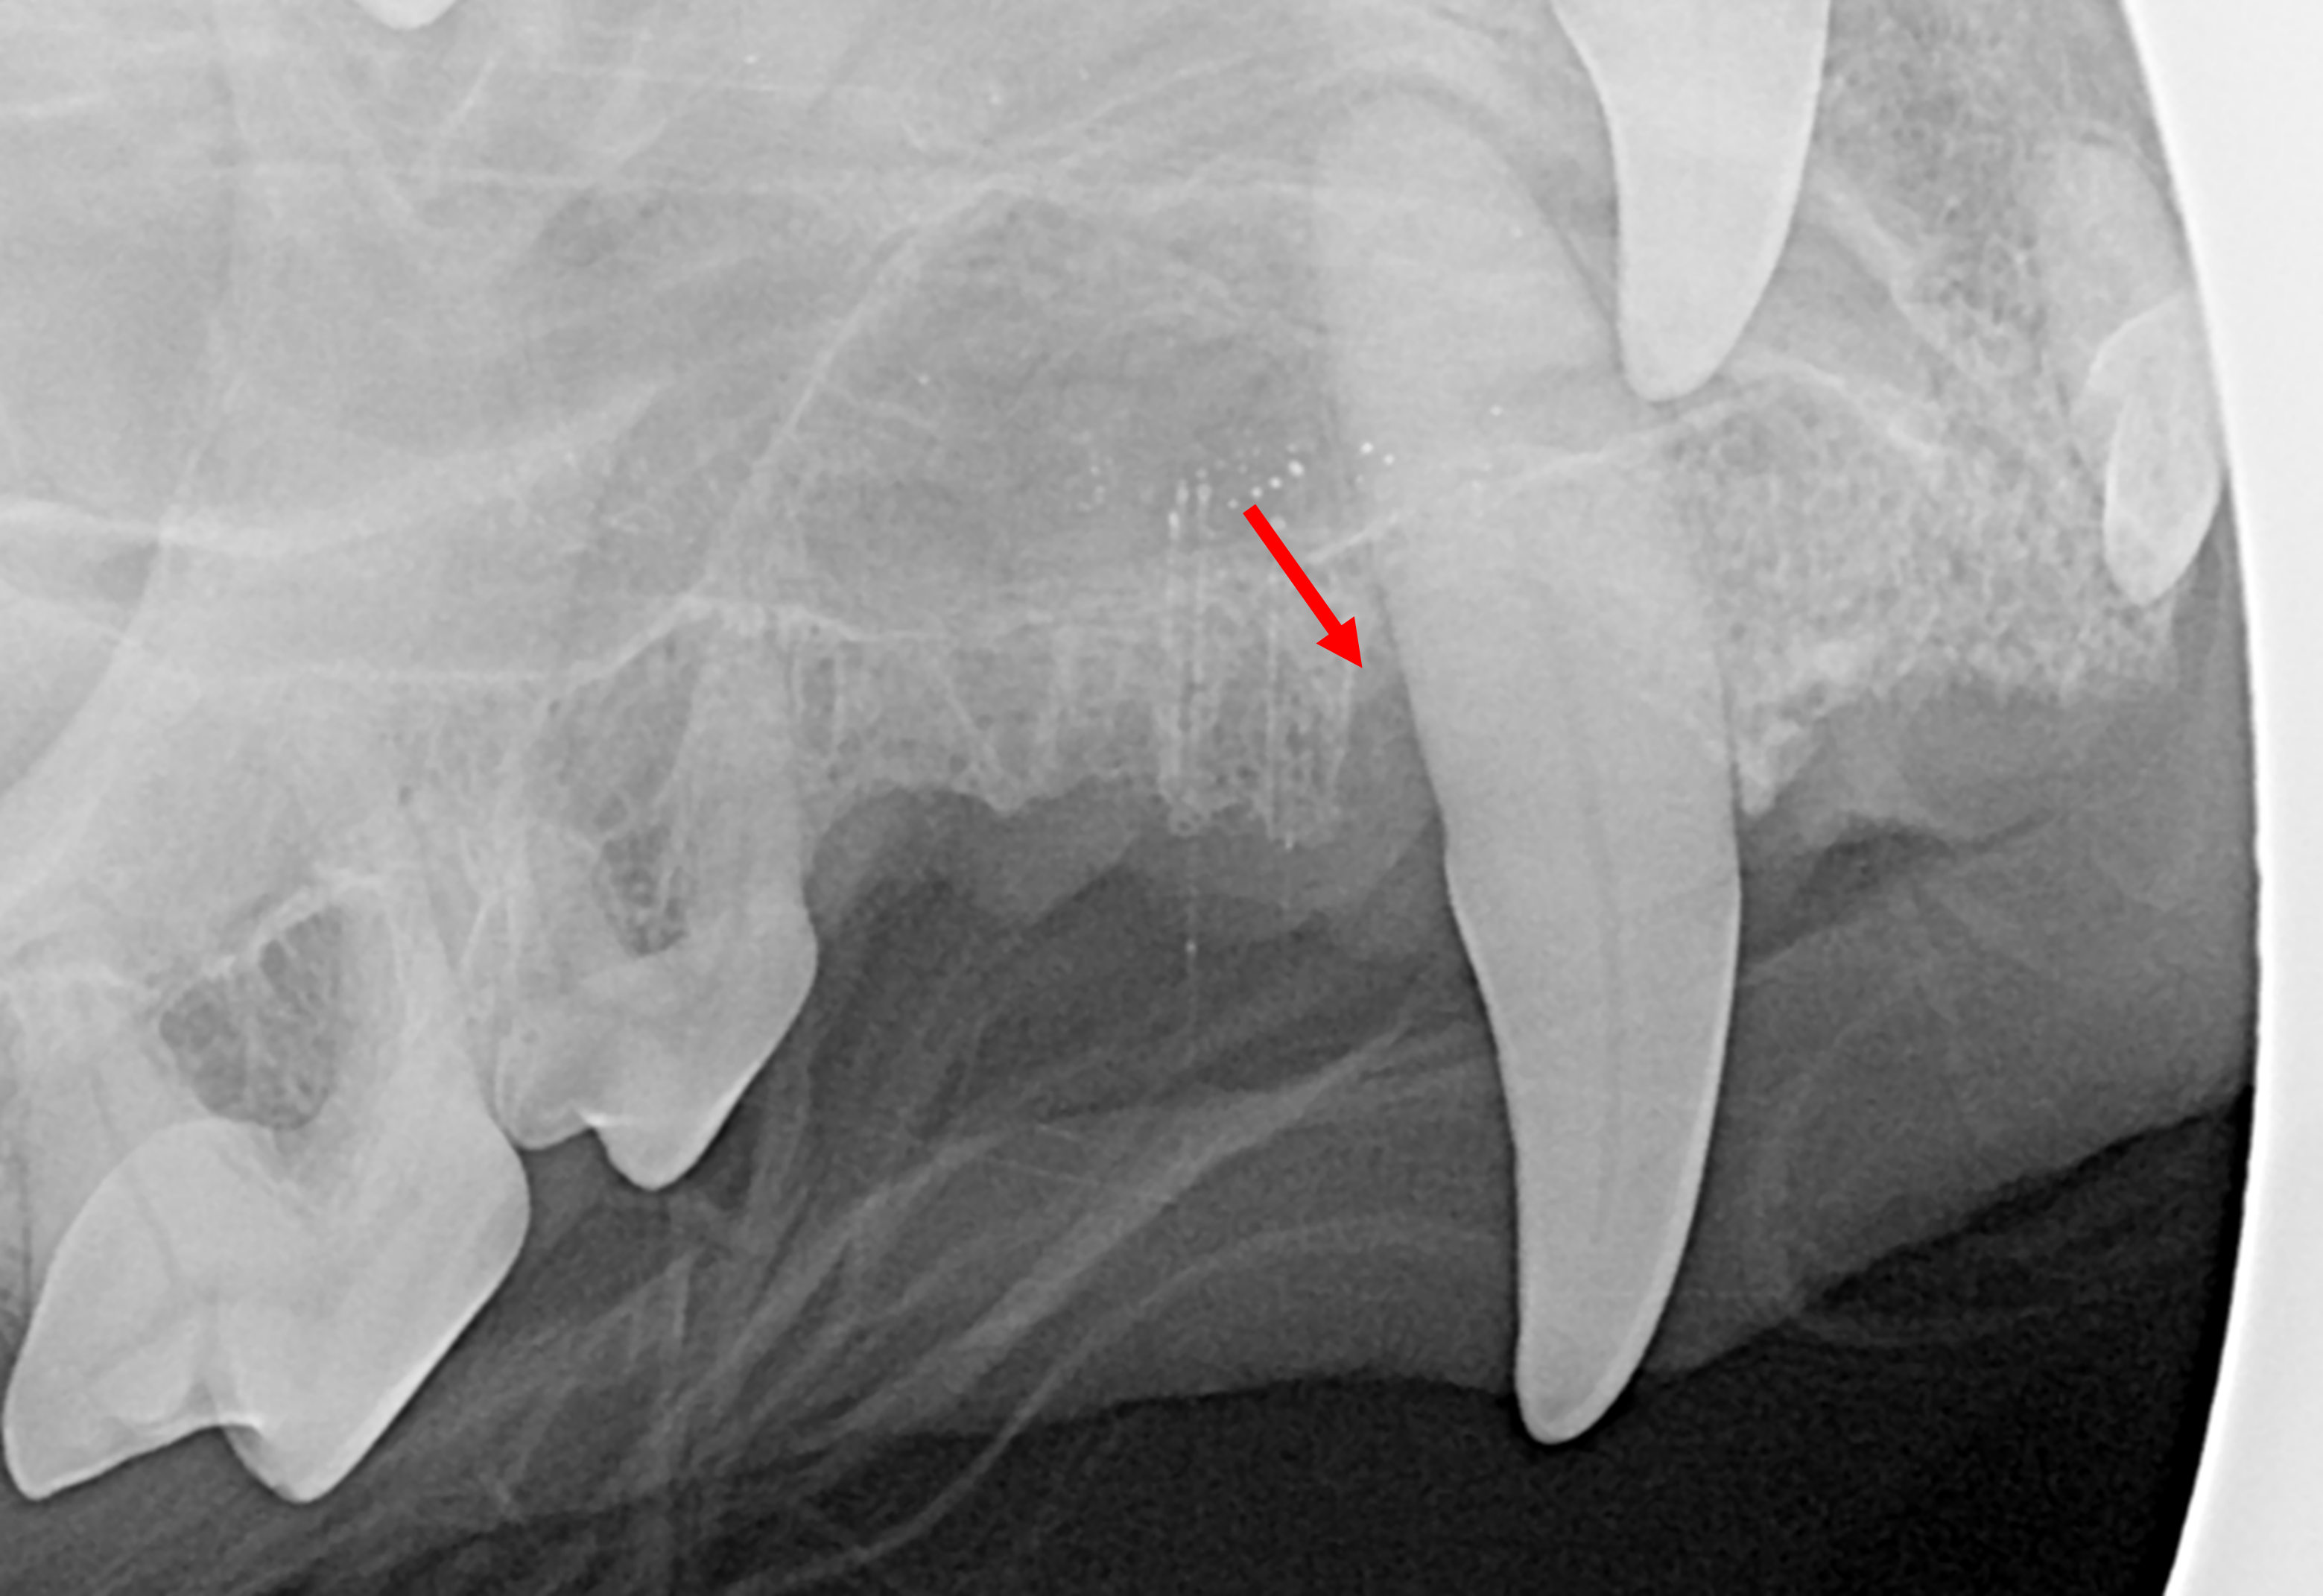

Advanced periodontal treatment is aimed at maintaining important teeth long term when they have certain types of periodontal disease.

The treatments can include bone grafting and guided tissue regeneration, as well as therapy for pocket reduction and for removal of excess gum tissue. Many of the treatments are very effective in the right pet and the right defect, but almost all will require a high-level home care following treatment. Guided tissue regeneration is not expected to succeed without daily toothbrushing. Follow-up professional care will also be required to ensure long-term success.